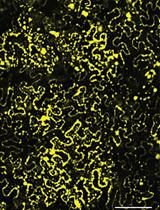

PLGA/PLA-PEG-FA 纳米颗粒的制备、表征和细胞摄取

Preparation, Characterization, and Cell Uptake of PLGA/PLA-PEG-FA Nanoparticles

Apr 5, 2022

Oral administration of colon-targeting nanoformulations holds many advantages over the systemic delivery of free drugs, or traditional nontargeting formulations in the treatment of ulcerative colitis (UC). Currently, the most conventional method for constructing colon-targeting drug delivery systems (DDS) is by integrating the biocompatible materials poly(lactic-co-glycolic acid) (PLGA) and polylactic acid (PLA) into a copolymer. This PLGA/PLA-polyethylene glycol-folic acid (PEG-FA) copolymeric nanoformulation effectively delivers the drugs for uptake by various human colon cancer cells (e.g., HT-29 and HCT-116) and mouse colon cancer cells (CT-26). There is, however, a distinct lack of comprehensive protocols for the construction of such copolymer. This protocol details an easy-to-follow single-step method for the construction of a colon-targeting PLGA/PLA-PEG-FA nanoformulation, which encapsulates a fluorescent dye and demonstrates the visualization of its cell uptake in vitro.